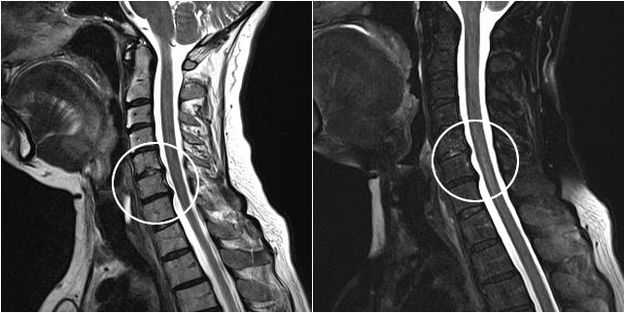

Modern diagnostic methods include MRI and CT scanning, which make it possible to most accurately examine the processes of destruction of cartilage and bone tissue.In addition, thanks to this technique, it is convenient to diagnose hernias and other soft tissue defects near the source of the disease.